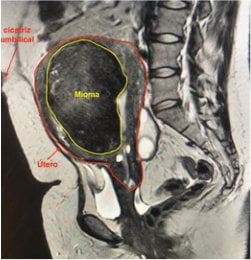

A partir dos dados clínicos e identificação de massa palpável ao exame físico, suspeitamos da doença, porém os exames de imagens são essenciais para o diagnostico e definição de tratamento.

Através da Ultrassonografia e Ressonância magnética de pelve é possível identificar e classificar os miomas, permitindo o planejamento do tratamento adequado.